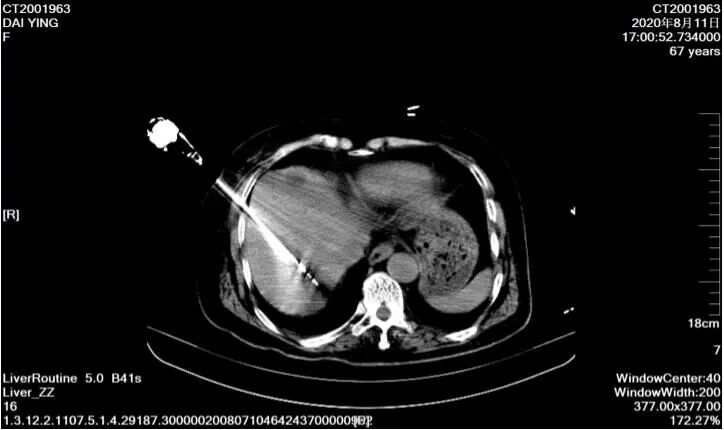

67歲女性,結(jié)腸癌術(shù)后肝轉(zhuǎn)移,行微波消融術(shù)將肝臟轉(zhuǎn)移灶清除,之后多次化療聯(lián)合免疫治療,目前病情控制可。